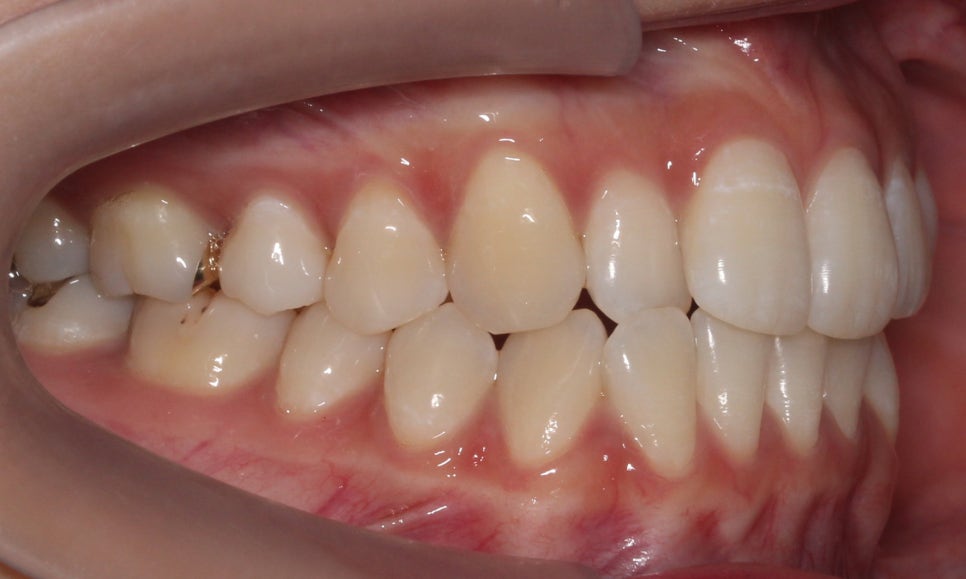

신논현치과 자가결찰브라켓 Case의

교정 전 치아 상태입니다.

정면에서 본 치아의 전체적인 모습을 보면

상대적으로 구치부보다 전치부의 치열이

삐뚤어져 있는 상태로 12번(측절치)의

반대교합이 눈에 띄는 모습입니다.

치아 개방 시 상악과 하악의 정중선을 보면

대각선으로 삐뚤어져 있는 것을 확인할 수 있는데요,

안모의 중심이 틀어져 있기 때문에 치아 개방-교합 시

한쪽으로 힘이 가중될 가능성이 있습니다.

overbite 사진을 보면 상악 좌측 측절치가

하악보다 뒤쪽으로 교합되는 모습을

확인할 수 있는데요, 이렇듯 일부 치아에

반대교합 증상이 나타날 경우 2D교정이나

투명교정을 통해 단기간에 심미적인

치아 교정이 가능합니다.

전치부의 돌출 정도를 확인할 수 있는

overjet 수치는 비교적 돌출감이 없는 모습으로

거꾸로 물리는 측절치를 해결한다면

스마일라인의 심미성을 보완할 수 있을 것으로 보입니다.

좌우의 교합평면을 보면 구치부의 교합은

크게 틀어진 부분 없이 양호한 상태인데요,

상악의 경우 송곳니의 위치나 각도도

좋기 때문에 부분교정도 가능하나

전체적인 교합을 바르게 하기 위해

자가결찰브라켓인 클리피씨교정 장치를

적용하여 전체교정을 진행하였습니다.

상악의 경우 설측으로 뻐드러져 있는

측절치의 바른 교정이 중요한 포인트이기 때문에

이를 중심으로 교정 계획을 수립하였습니다.